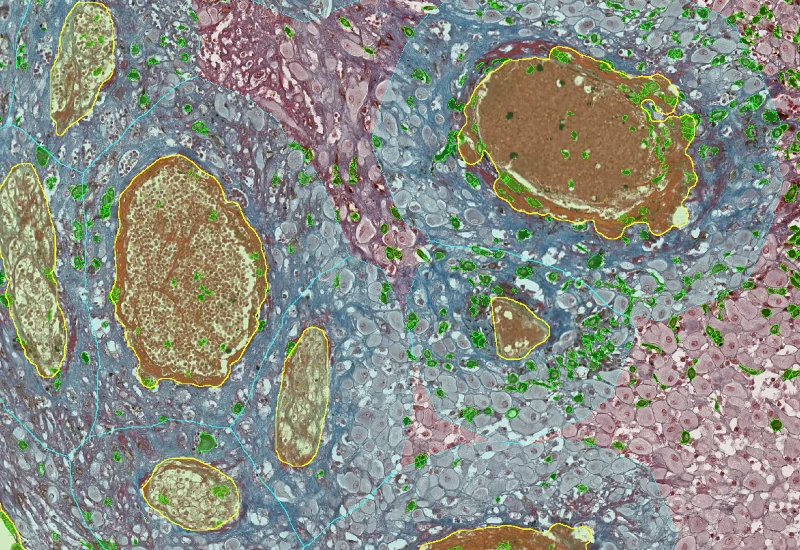

Sirius Red Angio

Detect Sirius Red–stained collagen and blood vessels, and quantify collagen area and total vessel count within the analyzed tissue.

The Angio Sirius Red App detects collagen based on Sirius Red staining as well as blood vessels. As outcome the APP outputs the area of Sirius Red stained collagen as well as the number of detected vessels.

vessel detection

Collagen detection